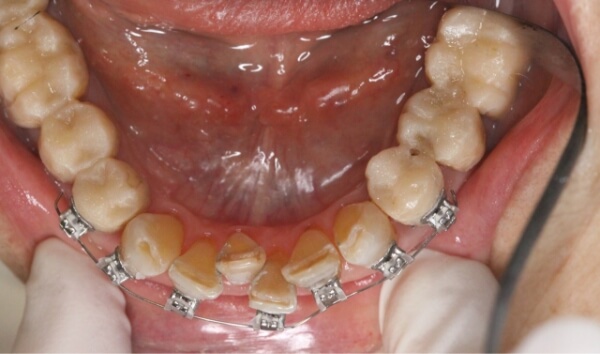

歯は削らずにブラケットを使用して、上下の前歯6本の隙間を閉じる治療を始めることになりました。

矯正装置(ワイヤーと審美ブラケット)をつけた当初は、少し痛みや違和感があったそうですが、歯が動き始めると痛みや違和感は次第になくなっていきました。

術中